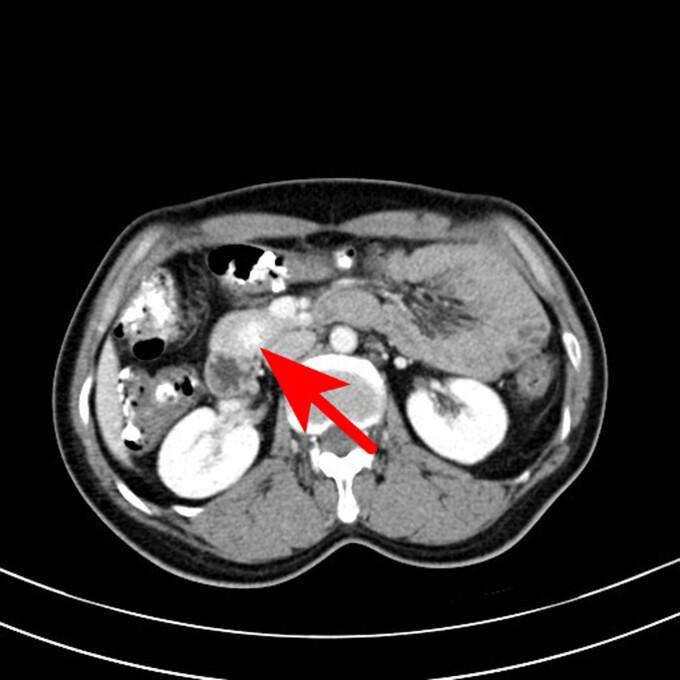

Ectopic thyroid is a rare malformation induced by a migration defect in the developing gland during embryogenesis. In 90% of cases, the ectopic thyroid is located in the lingual region, whereas it is extremely rare in the abdominal cavity, particularly in the pancreas. A 50-year-old female patient presented to the Taizhou First People's Hospital with a complaint of recurrent mid-lower abdominal pain and diarrhea for approximately a month. The abdominal computed tomography scan revealed a space-occupying lesion with abundant blood supply in the head of the pancreas during the consultation. This led to the suspicion of a neuroendocrine tumor. The doctor considered that this lesion in the head of the pancreas could be responsible for the patient's incontinence. A laparoscopic pancreaticoduodenectomy was performed after relevant tests were undertaken and contraindications were ruled out. The patient was diagnosed with ectopic thyroid of the pancreas through postoperative pathology. Ectopic thyroid can be considered in middle-aged and elderly women who present with a mass with abundant blood supply and an unknown diagnosis. Subsequent treatments should be decided after fine-needle aspiration cytology.